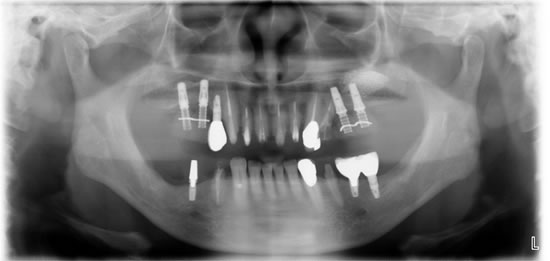

この患者さんは、以前から何回も奥歯が腫れたり、前歯の被せものが取れたりしていました。今回はお口全体をしっかり治療したいとうことで来院しました。

問題点は咬み合わせが崩壊しているため、咬合再構成しないといけないことと、以前にインプラント治療がされているので、咬合再構成するときお口にはいっているインプラントをどのように対応するかです。

治療中

現在プロビジョナルレストレション(治療用の仮歯)で咬み合わせを変え経過をみています。上顎奥歯のインプラント治療には骨が不足しているためサイナスリフトを併用しています。この仮歯をベースにして、最終的な被せものを製作していきます。